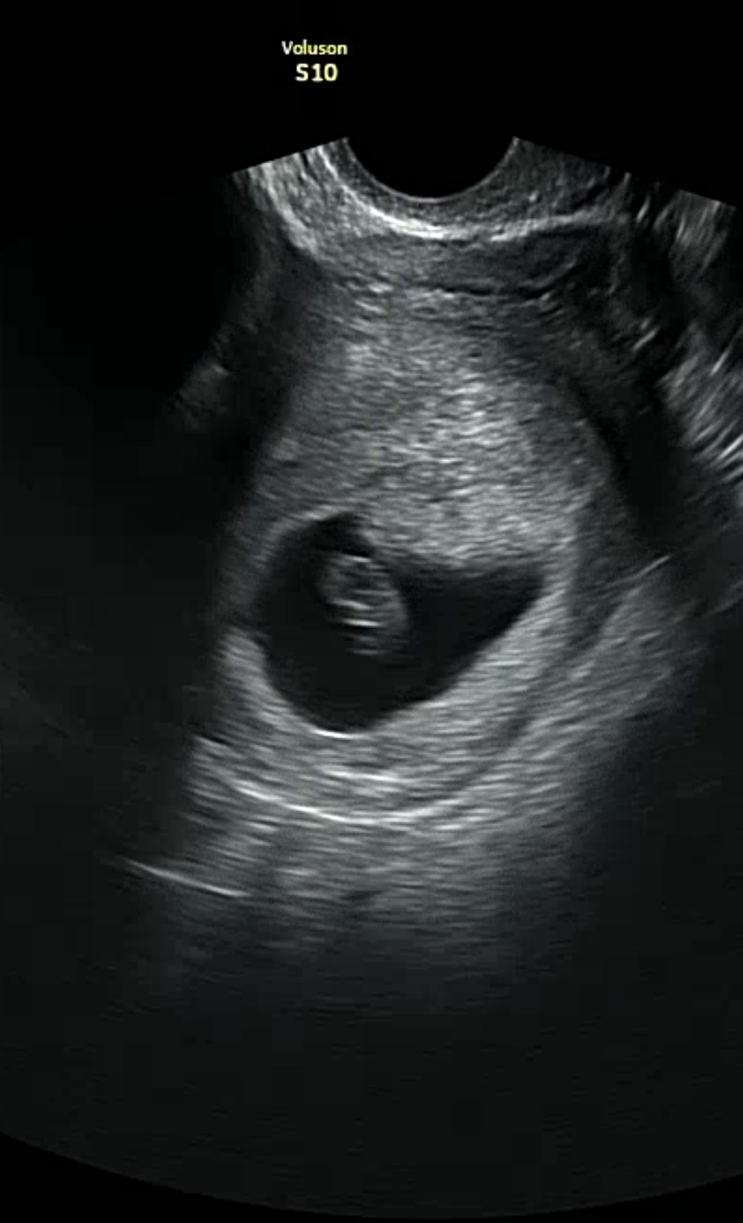

[임신극초기 6,7주차]선홍빛 피비침,병원 입원, 유산방지주사, 임신물혹

임신이 처음이라... 산부인과 의사샘이 많이 걷지말라고 충고를 하였는데.. 별 생각이 없이 이틀연속 팔천...

[임신극초기 5주차] 초음파검사, 자궁 물혹, 입덧

5,6주차부터 드디어 질초음파로 자그마한 생명을 볼 수 있었당! 너무 자그마해... 난황이 하트모양으로 있...